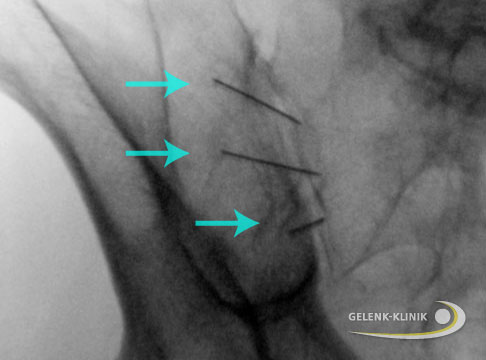

Je nach geplanter Einstichstelle wird der Patient gelagert. Bei einem Sakralblock liegt der Betroffene auf dem Bauch, wird die Wirbelsäule weiter oben infiltriert, sitzt der Patient mit vorgebeugtem Oberkörper. Nach Desinfektion der Einstichstelle führt der Arzt die sehr dünne Hohlnadel ein und schiebt sie unter Röntgenkontrolle bis an die betreffende Stelle vor. Meist wird dann durch die Nadel ein Kontrastmittel injiziert, um im Röntgenbild die korrekte Lage der Nadelspitze zu überprüfen. Danach spritzt der Arzt das Medikament oder - wenn nötig - auch ein Medikamentengemisch.

Zwischen den Wirbeln sitzen kleine Gelenke, die Facettengelenke. Mit zunehmendem Alter können sie verschleißen und Rückenschmerzen verursachen. Man spricht von Facettengelenksarthrose oder Spondylarthrose. Hier kann die gezielte Infiltration Entzündung und Schmerzen lindern. Gespritzt wird meist eine Mischung aus entzündungshemmendem Kortison und lokalem Betäubungsmittel (Lokalanästhetikum). Ob die Nadel richtig sitzt, kontrolliert der Arzt meist mithilfe eines Röntgenbildwandlers. In manchen Häusern wird stattdessen auch sonographiert oder eine Computertomografie durchgeführt.

Periradikuläre Infiltration

Bei diesem Verfahren spritzt der Arzt das Medikament in den Bereich der Wirbelsäule, wo die Nervenfasern in das Rückenmark ein- und austreten (Nervenwurzel). Dadurch lassen sich Nervenschmerzen lindern, die durch Druck auf die Wurzel eines Spinalnervs ausgelöst werden. Typische Ursachen sind ein Bandscheibenvorfall oder eine Bandscheibenvorwölbung. In manchen Fällen lässt sich durch die periradikuläre Infiltration eine Operation vermeiden, zumindest aber die Zeit bis zum chirurgischen Eingriff möglichst schmerzfrei überbrücken.